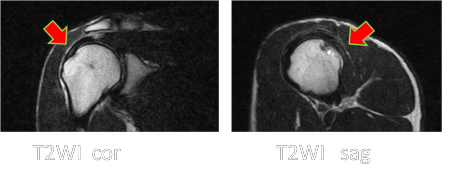

投球側の腱板には無症状にもかかわらず48%の選手に異常所見を認めました。

非投球側と比べその頻度は有意に高く認められました。

所見のパターンは腱板に巣状の高信号域を認めました。

所見の分布は腱板の棘上筋-棘下筋の移行部に集中していました。